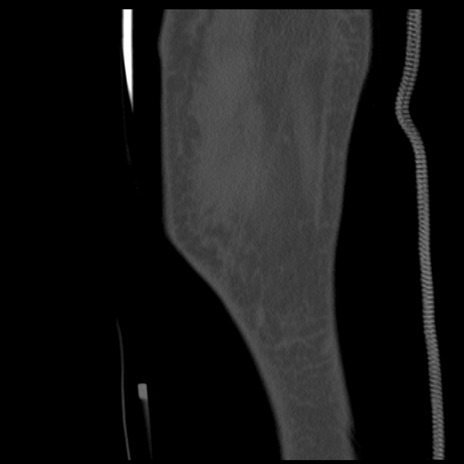

症例28 右膝関節CT(矢状断像)

右膝関節CT

冠状断像